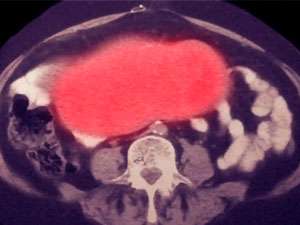

Eksperimental rak terapiýasyny alanyndan 10 ýyl geçse-de, leýkemiýa pasiýenti Doug Olsonda rak keselinden nam-nyşan görünmeýär.

Olsonyň wakasy alymlaryň CAR-T öýjük terapiýasynyň güýjüne we onuň täsiriniň uzak wagt dowam etjegine bolan ynamyny artdyrdy. Adatça rak keselinden gutulýan az, emma CAR-T öýjük terapiýasy ragy bejermäge umyt berýär.